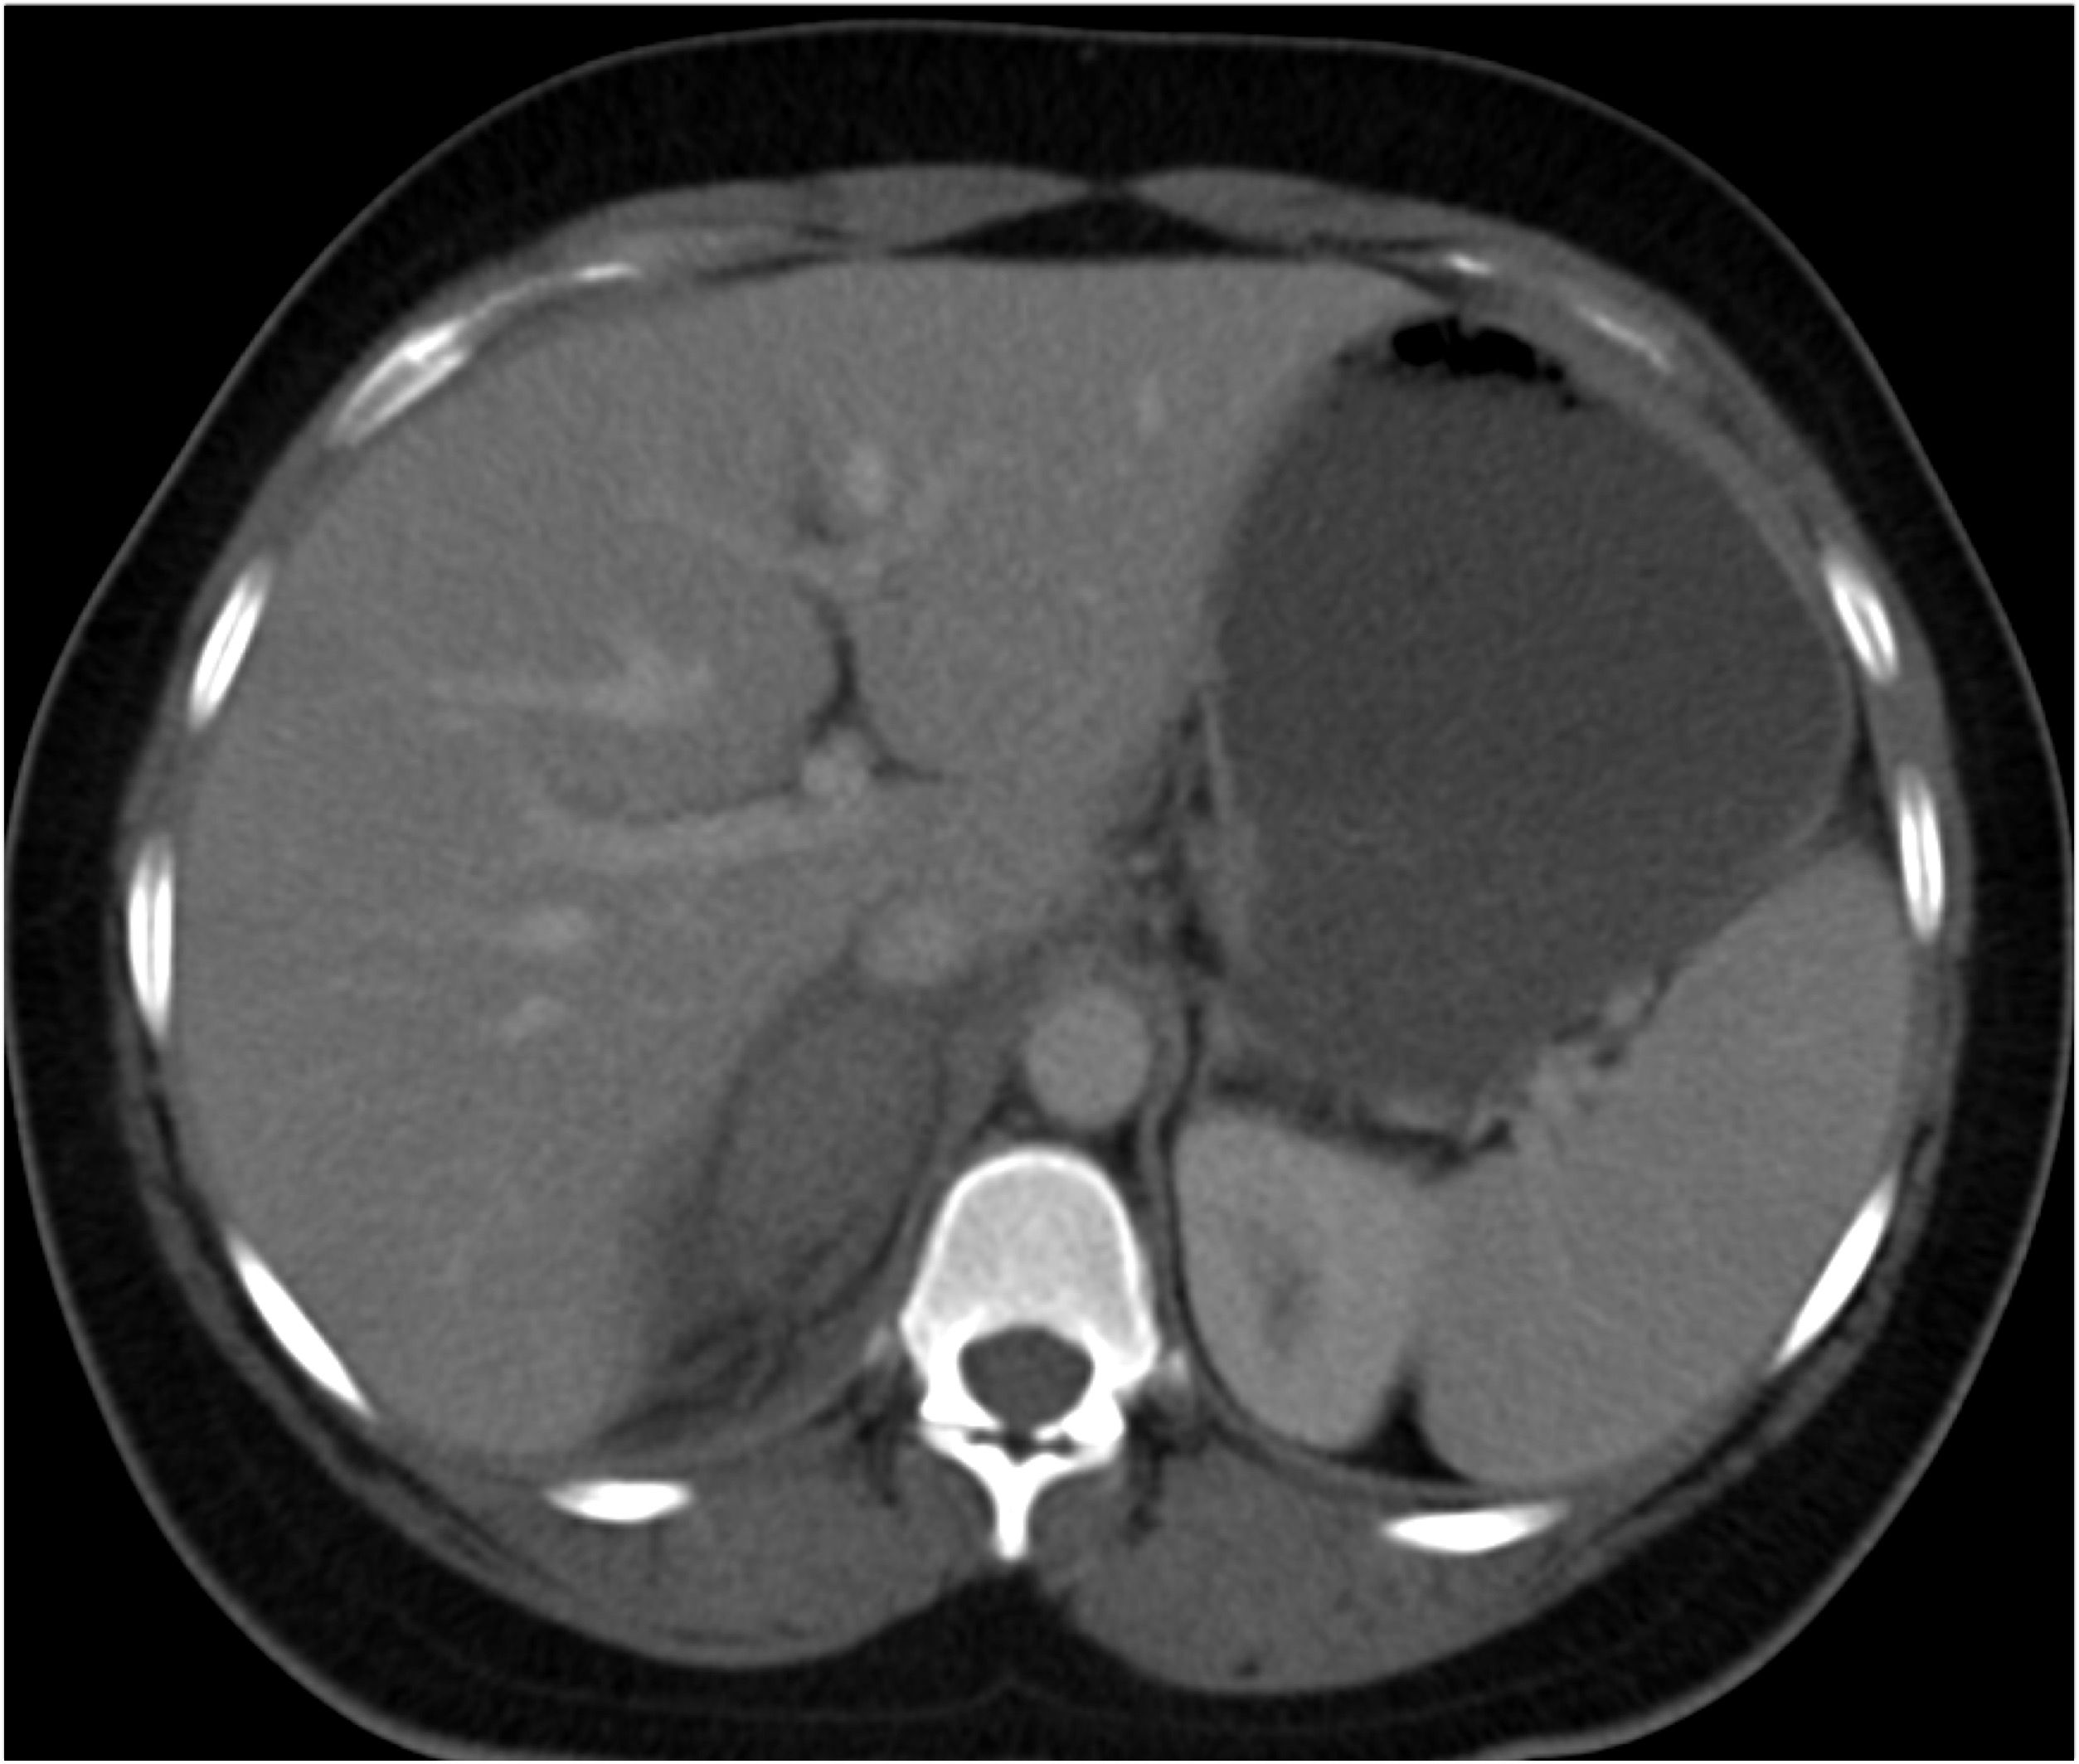

6) The most likely diagnosis in this case is?

lymphoma

acute pyelonephritis

XGP (xanthogranulomatous pyelonephritis)

TB